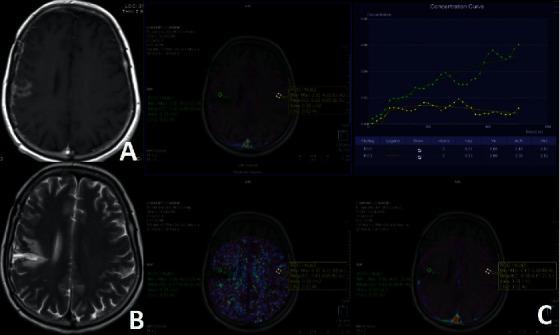

Follow-Up of High-Grade Glial Tumor; Differentiation of Posttreatment Enhancement and Tumoral Enhancement by DCE-MR Perfusion.

To search for the utility of DCE-MRP to differentiate between posttreatment enhancement (PT) and tumoral enhancement (TM) in high-grade glial tumors.

Thirty-four patients with glioma (11 grade 3; 23 grade 4) were enrolled. Enhancement in the vicinity of the resection cavity demonstrated by DCE-MRP was taken into consideration. Based on the follow-up scans, reoperation or biopsy results, the enhancement type was categorized as PT or TM. Measurements were performed at the enhancing area near the resection cavity (ERC), nearby (NNA) and contralateral nonenhancing areas (CLNA). Perfusion parameters of the ERC were also subtracted from NNA and CLNA. Intragroup comparison (paired sample -test) and intergroup comparison (Student's -test) were made.

There were 7 PTs and 27 TMs. In the PT, the subtracted values of Ve and IAUC from the CLNA and NNA and the subtracted value of Kep from NNA were statistically different. In TM, all metrics were significantly different comparing the CLNA and NNA. Comparing PT with TM, Ktrans, IAUC, Kep, and subtracted values of Ktrans and IAUC from both NNA and CLNA were significantly different.

In PT, only Ktrans values did not reveal any difference comparing NNA and CLNA. To differentiate PT from TM, Ktrans, Kep, IAUC, and subtracted values of Ktrans and IAUC from NNA and CLNA can be used. These findings are in concordance with literature.